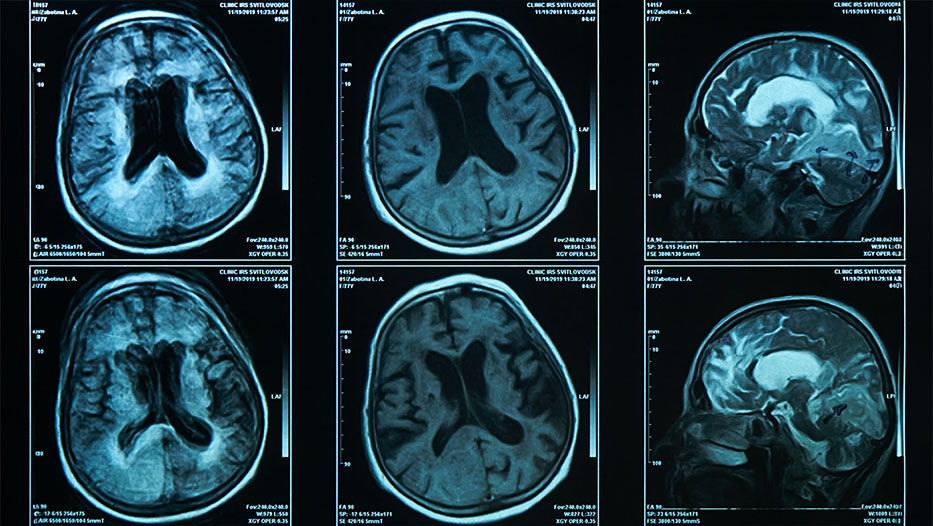

A brain scan on magnetic resonance imaging MRI film, for neurological medical diagnosis of brain diseases like FTLD and Alzheimers, which can lead to PPA

PPA occurs when harmful proteins accumulate in the brain areas that control language, gradually damaging and killing brain cells.

Most cases are caused by a brain disease called FTLD, while Alzheimer's disease causes the rest.